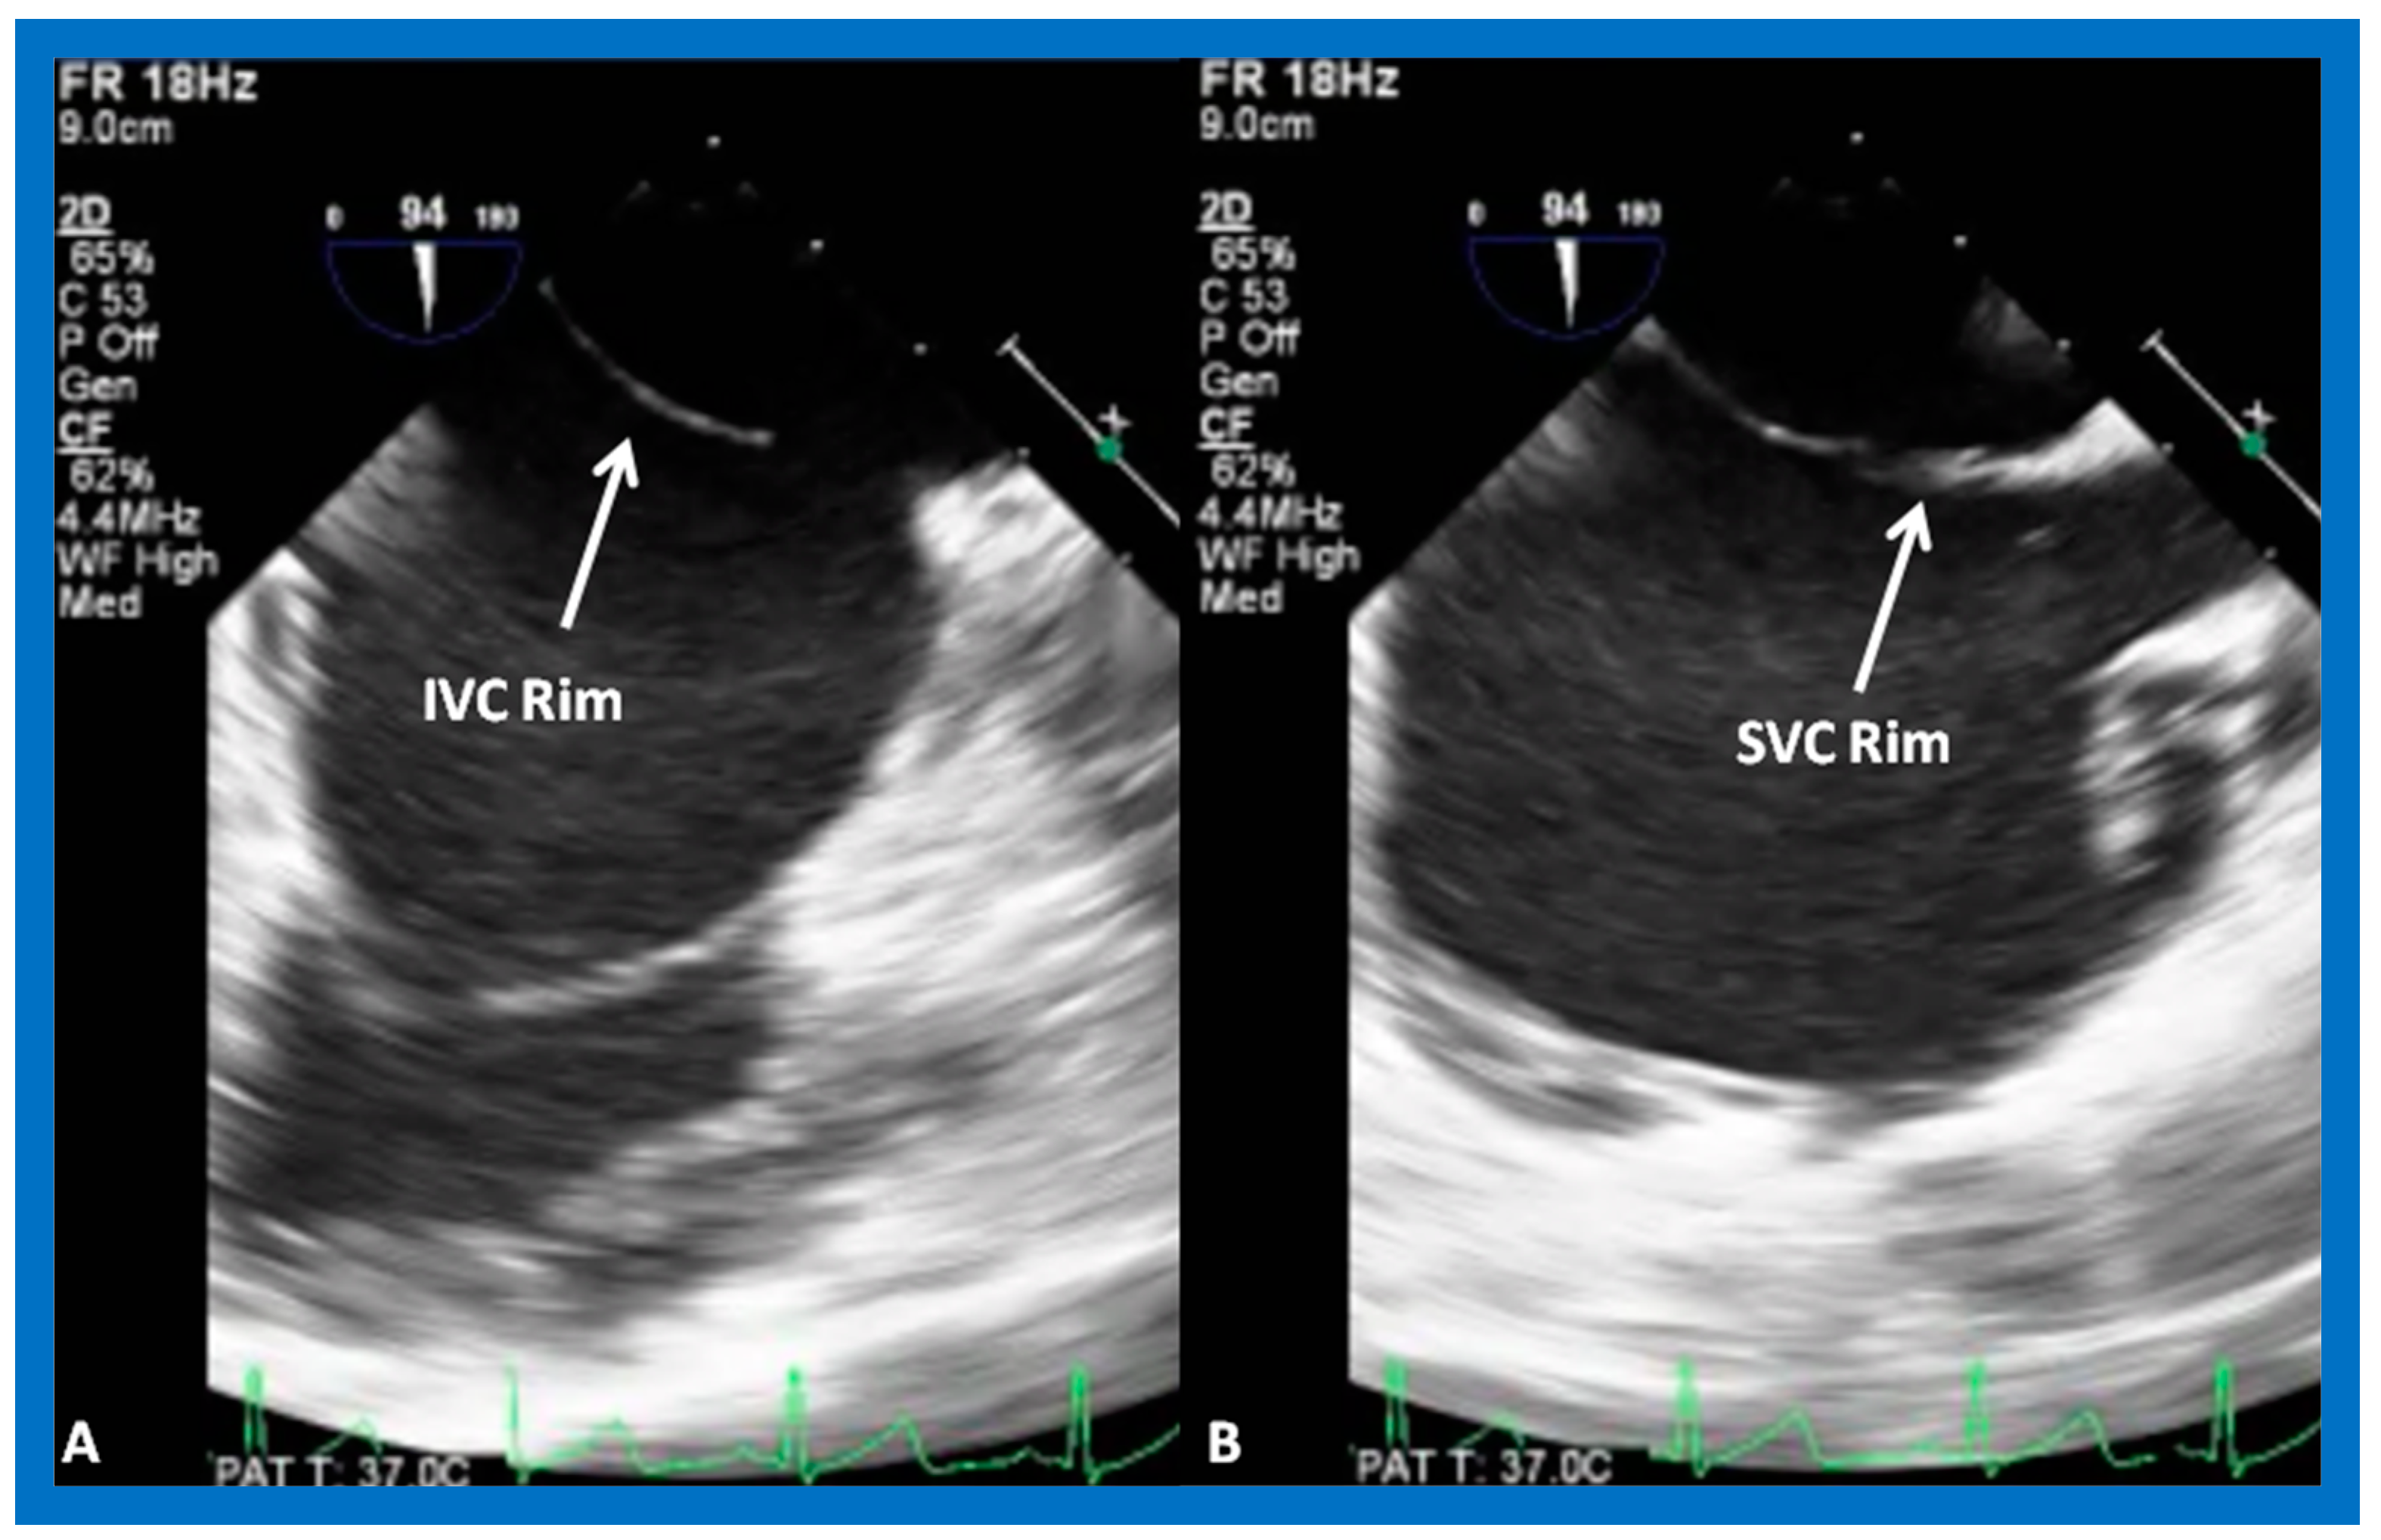

4. Patient Selection for Device Occlusion

8.5. Septal Rims